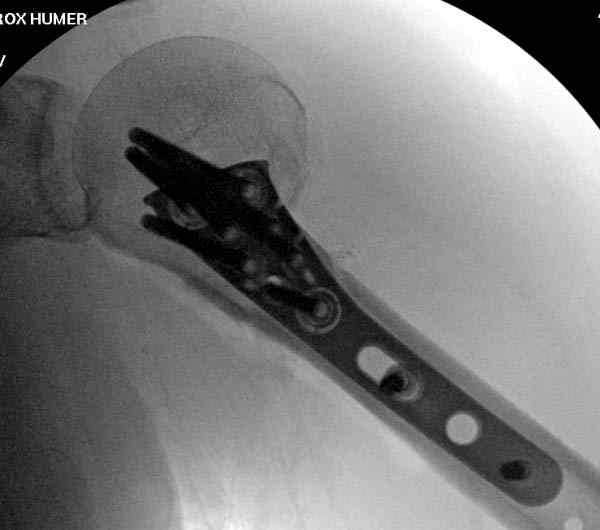

Здесь пример открытой репозиции 57 летнего с переломом плеча (1,2) смещение обнаружено на интероперационном снимке. При нормальной прямой проекция (3) угловое смещение обнаружили в аксиальной проекции (4)

После устранения смещения пластина установлена выше (5,6,7) и финальные снимки (8,9,10)

Подбор импланта тоже имеет значение, например многие импланты направлены для фиксации перелома без учета ротаторной манжетки. Предпочтительными являются низко сидящие полиаксиальные пластины, где верхние шурупы можно проводить под углом в 120 градусов. (11)

Пластина от Synthes или ее копии (надеюсь простят критику друзья из Деоста) считаются трудным из-за обширности доступа, особенно при установке верхне-заднего шурупа, где доступ надо расширять в верхнем отделе до ротаторной манжетки. Верхне сидящие импланты предназначены для проведения опоры (buttress) за бугристость плеча, но тогда приходится сталкиваться с подакромиальным импинжментом.